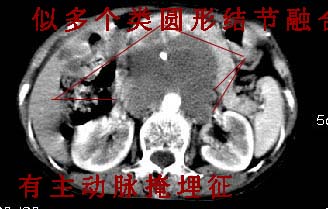

我的第1诊断还是考虑是淋巴类病变1}。从病灶形态上看不是很规则,但其更向是多个结节的融和,其内有少许坏死,整个病灶的强化不是很明显,临近左恻肠间隔有增厚,2}我认为更重要的一点的是肠系膜有明显增厚呈片状。3}患者的脾脏不大其未见异常病灶。结合以上几点我首先考虑是转移性{但对此诊断我觉得不足之处;转移性的淋巴结肿大融合为什么没有坏死?}。{另外患者无大便习惯改变及血便,其发现右颈包块在今年过年无意发现}。以上是我的浅分析望各位战友继续讨论!谢谢!!

主动脉-胰腺间隙可见巨大分叶状软组织肿块影,包绕腹主动脉、腹腔干及其分支、腔静脉等大血管,增强呈无明显强化,临近脏器明显受压移位,增强示有分界。肝右叶可见局限性低密影,边缘清楚。

影象表现:平扫,首先可见胃壁明显增厚,内外边缘清晰,外缘光滑,内边缘不归整,同时胃腔明显缩小。

讨论:首先看肠系膜和腹膜后的肿块我认为是多发融合的肿大的淋巴结。理由1大小不等的分叶,分布比较

自由。2其中的包绕的血管和周围少量的脂肪即所说的。

同时胃的影象表现和临床的不典型表现,所以我认为淋巴瘤,临床表现不支持胃癌